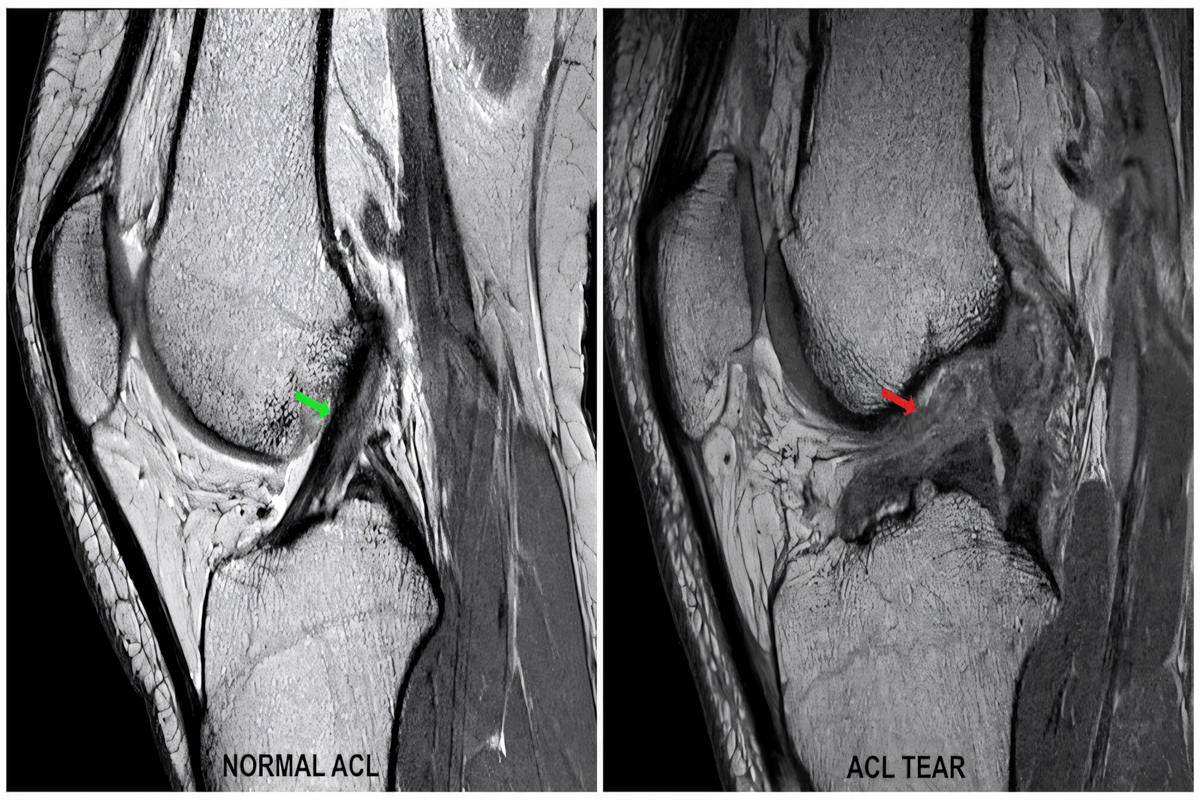

Απεικονιστικός έλεγχος

Ακτινογραφίες για αποκλεισμό οστικών κακώσεων

Μαγνητική τομογραφία (MRI), που επιβεβαιώνει τη ρήξη πρόσθιου χιαστού και αναδεικνύει συνοδές βλάβες σε μηνίσκους, χόνδρο ή πλάγιους συνδέσμους

Η MRI αποτελεί την εξέταση εκλογής για την τεκμηρίωση της βλάβης.